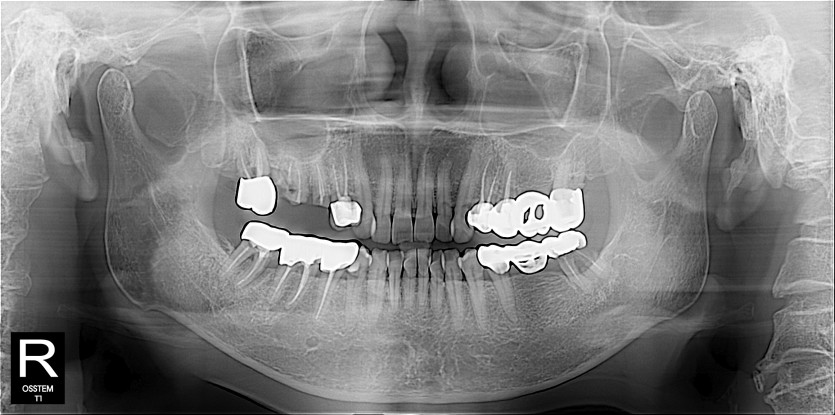

임플란트 사례